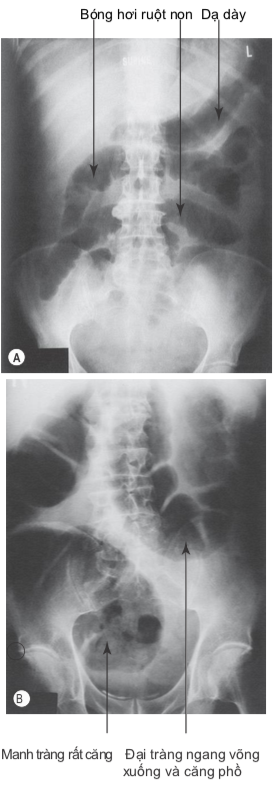

x quang tắc ruột

Nghi ngờ tắc ruột nếu đau bụng quặn từng cơn kết hợp nôn, bí đại tiện và/hoặc chướng bụng. Những triệu chứng nổi bật sẽ thay đổi dựa trên vị trí tắc nghẽn, nếu tắc ruột non cao thì nôn và đau bụng là ưu thế, ngược lại, nếu tắc đại tràng thấp thì táo bón và chướng bụng biểu hiện rõ hơn. Nếu có bất kỳ biểu hiện nào kể trên, chụp xquang bụng để giúp xác định chẩn đoán và ước tính vị trí tắc.

Kiểm tra xem có thoát vị nghẹt không ở bất kì bệnh nhân nào nghi ngờ tắc ruột non. Xem xét các chẩn đoán hình ảnh bổ sung và thăm trực tràng để xác định tắc ruột và phân biệt với tắc nghẽn giả (pseudo-obstruction) ở bệnh nhân tắc ruột già.